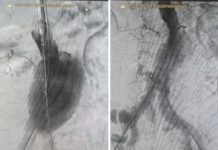

Если говорить про Волжский, то за последние годы вливания в модернизацию системы здравоохранения города в рамках губернаторской программы составили более 9,5 млрд рублей. В 2019 году начался ремонт больницы им.Фишера, где предоставляются медуслуги не только жителям нашего города, но и районов Заволжья. Были обновлены поликлиника, женская консультация, отделения стационара больницы, открыты современный центр амбулаторной онкологической помощи и региональный сосудистый центр. До конца нынешнего года здесь планируется завершить ремонт и привести в порядок прилегающую территорию.